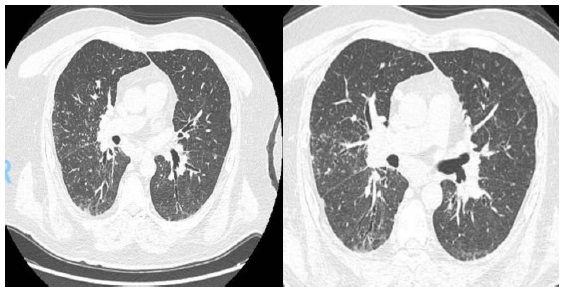

La sarcoidosis pulmonar se caracteriza por varios hallazgos en la tomografía computarizada de alta resolución (TCAR). Estos incluyen linfadenopatía hiliar y paratraqueal bilateral bien definida, opacidades nodulares y micronodulares con distribución perilinfática. Los nódulos son redondeados y suelen tener un tamaño de 2 a 4 mm. También se observa el agrandamiento y calcificación de los ganglios linfáticos hiliares bilaterales. Las calcificaciones pueden presentar diferentes aspectos, como amorfo, puntiforme (parecido a una palomita de maíz) o similar a una cáscara de huevo. La distribución perilinfática de las lesiones micronodulares es el patrón parenquimatoso más frecuente. Con el tiempo, estas lesiones pueden fusionarse y formar macronódulos y conglomerados similares a masas, con la presencia de pequeños nódulos satélites alrededor de las masas conglomeradas, lo que se conoce como “signo de galaxia”.

En la TCAR se pueden encontrar otros hallazgos menos frecuentes, como cambios fibróticos con opacidades lineales y bronquiectasias por tracción, opacidades parcheadas en vidrio esmerilado, consolidación parcheada del espacio aéreo (alveolitis sarcoide o sarcoidosis alveolar), opacidades reticulares lineales aisladas, halo inverso o signo del atolón. La sarcoidosis pulmonar también muestra un patrón de atenuación en mosaico debido a la afectación granulomatosa o fibrosis de las vías respiratorias pequeñas, lo cual puede estar asociado con obstrucción en las pruebas de función pulmonar. El atrapamiento de aire es común pero no específico de la sarcoidosis y puede estar presente en cualquier etapa radiográfica de la enfermedad. Se detectan anomalías traqueobronquiales en la TC, con engrosamiento y estenosis de la pared bronquial, que se correlacionan con los hallazgos broncoscópicos.

En la tomografía computada de tórax en ventana pulmonar se identifica un patrón micronodular con distribución perilinfática y difusa en ambos hemitórax. Este hallazgo se acompaña de un engrosamiento peribronquial notable, así como de opacidades en vidrio deslustrado, que predominan en las zonas subpleurales y en las regiones posteriores de ambos pulmones.